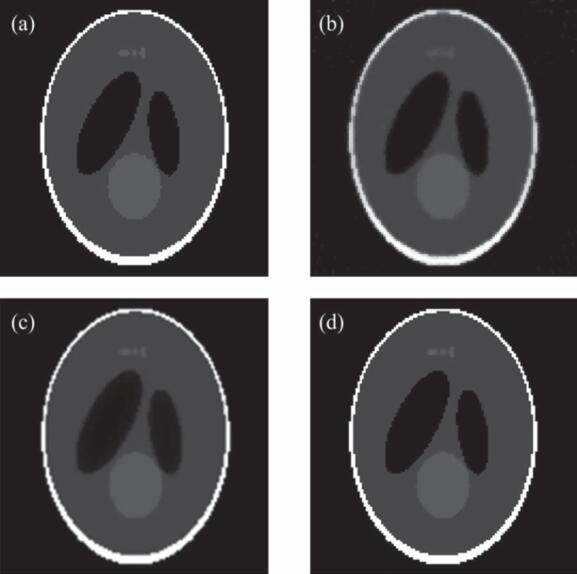

实验结果表明:与解析重建算法FDK相比,提出的算法在投影数较少的情况下,仍能获得较好的重建图像质量(见图1);与两种现有的基于TV正则化的迭代重建算法(ASD-POCS,EM-TV)相比,所提算法收敛速度提高6倍以上,且表现出更强的图像去噪和边缘保持能力(见图2)。此外,采用GPU加速手段使得上述迭代算法的重建时间大为减少(见表1)。

图2. 经典迭代算法与3DA-TVAL3算法的重建结果。(a)Sheep-Logan体模的原图像;(b)ASD-POCS算法的重建结果;(c)EM-TV算法的重建结果;(d)3DA-TVAL3算法的重建结果。